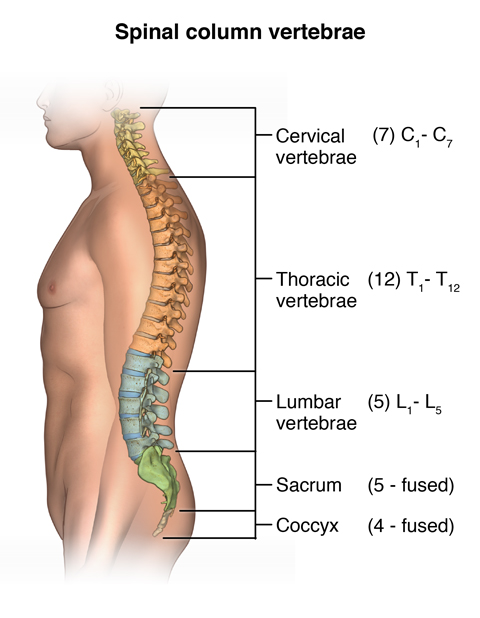

X-ray record with contrast of the spinal cord. Myelograms can show disorders of the spinal cord and nerves in the spinal canal. The vertebrae spinal bones orange protect and support the spinal cord.

At the base of the vertebral column is the sacrum the bone that links the vertebrae to the pelvis. A spinal cord injury is typically diagnosed with MRI. Congenital hernia protrusion of the spinal cord and meninges through a defect gap in the vertebral column.

The Lumbar Spine Sacrum And Coccyx Dance Advantage Lumbar Spinal Stenosis Spine Surgery Spinal Fusion